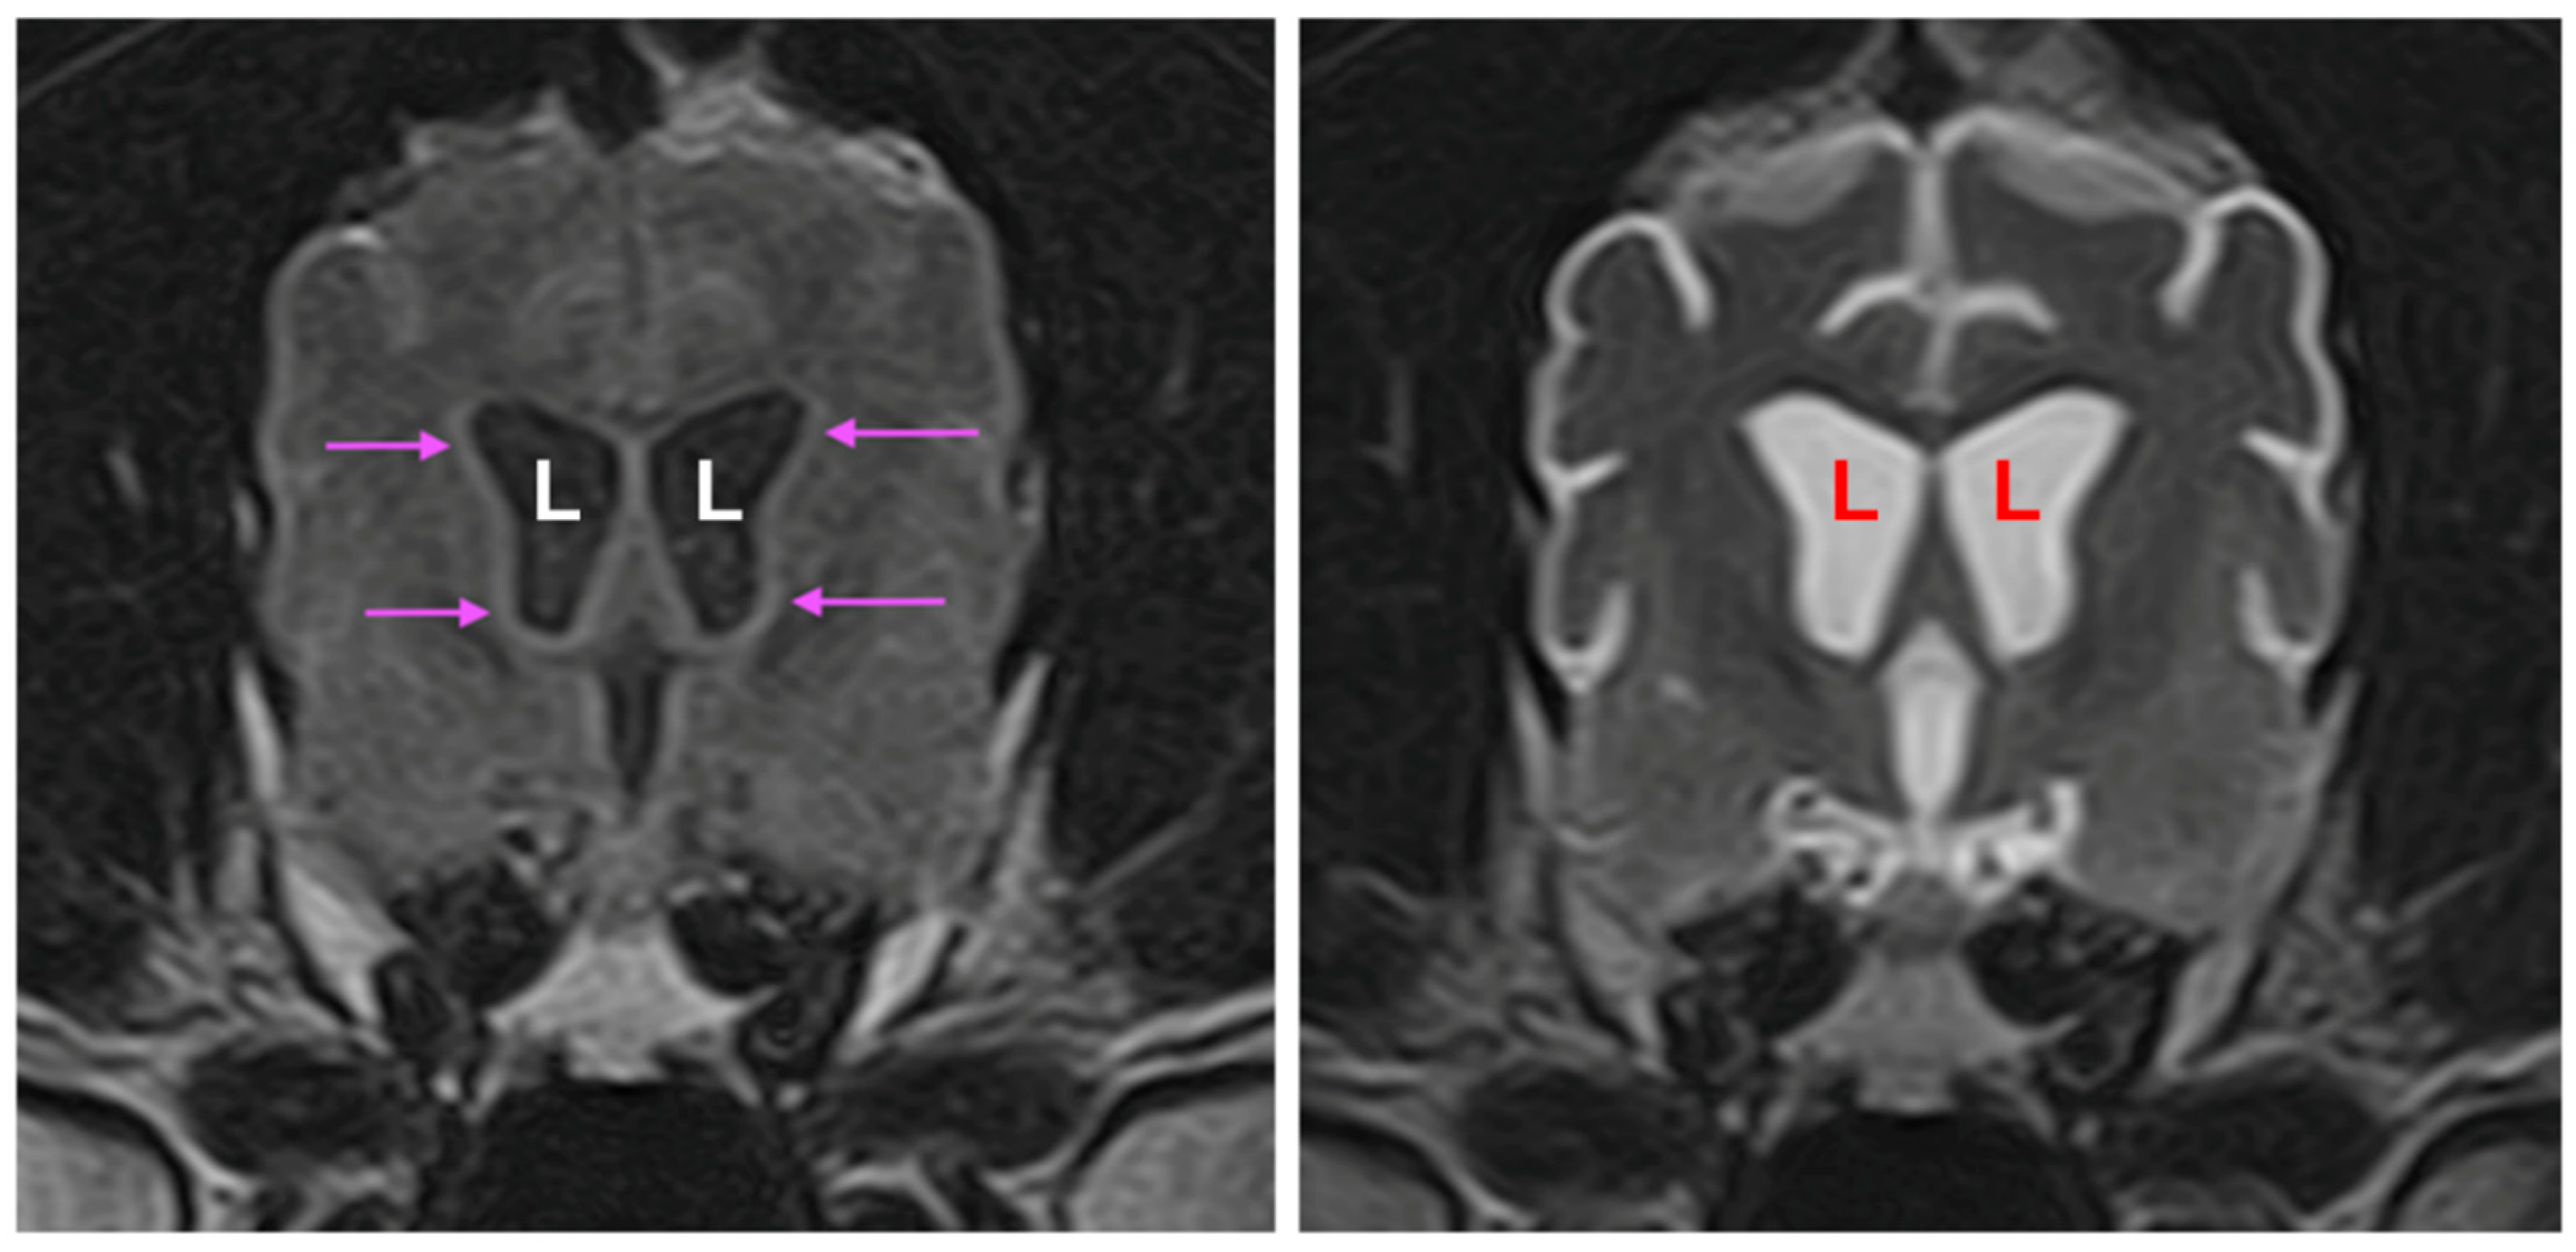

3.1. Disease Phenotype

3.2. Microscopic Findings